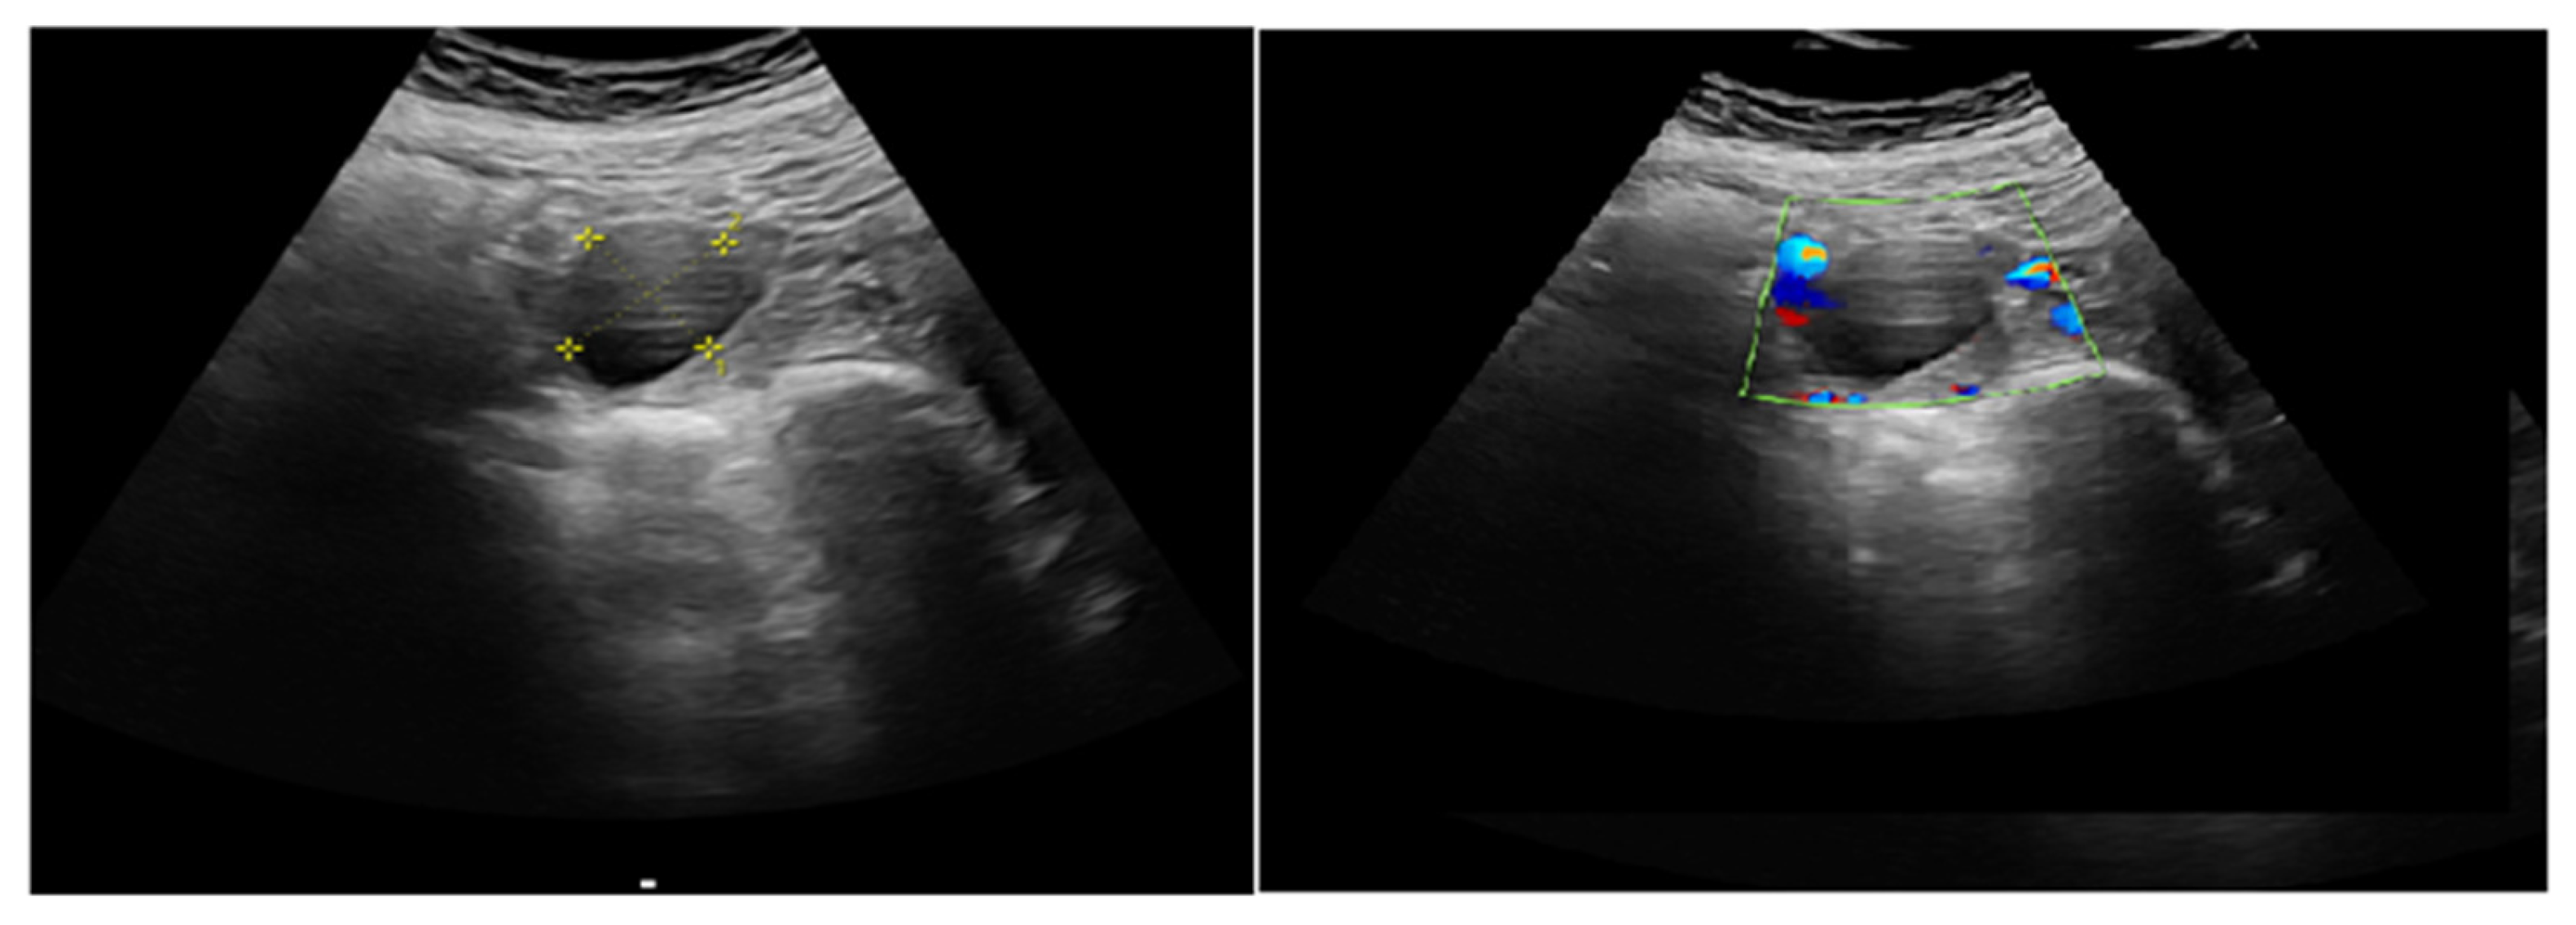

2.3.1. Corpus Luteum (CL) Localization and Identification

2.3.2. Doppler Measurement Procedure